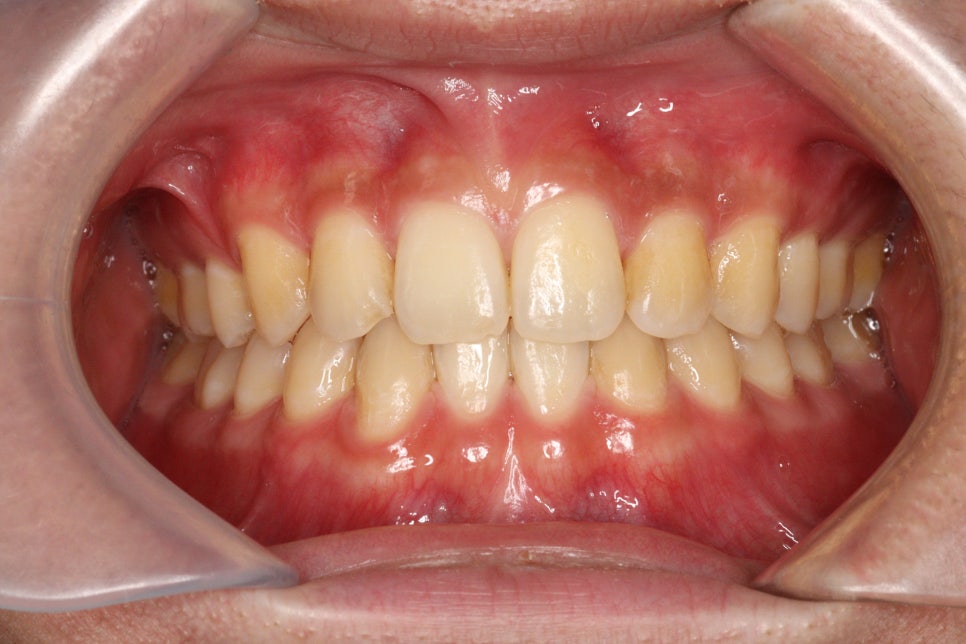

이 친구는 약간의 돌출도 보이고 있었기 때문에 위쪽 치아를 두개 발치했었습니다.

약2년의 치료기간이 걸렸으며 올해 초에 정기검진을 왔습니다

치료가 끝난지 약 3년정도 지난 모습인데 긴밀한 교합으로 인해 치료결과가 잘 유지되고 있는 것 같습니다.